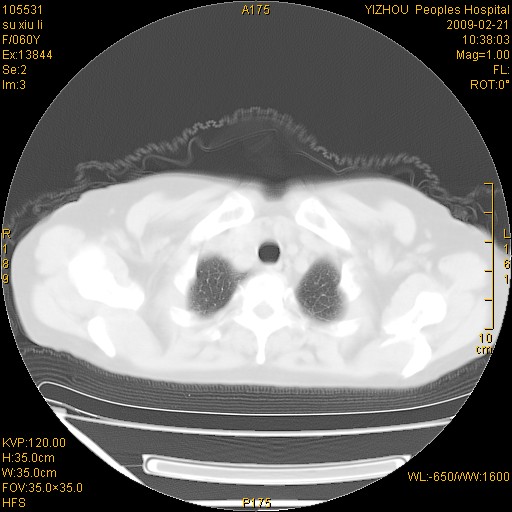

标题: CT18259:两肺间质纤维化? [打印本页]

标题: CT18259:两肺间质纤维化?

女,60岁,反复咳嗽1月。

两肺支扩,以肺为著合并双肺较广范纤维化病变。建议除外结核等病变。

间质性肺炎

符合间质感染,部分纤维化表现

特发性间质纤维化

特发性间质纤维化伴支扩!